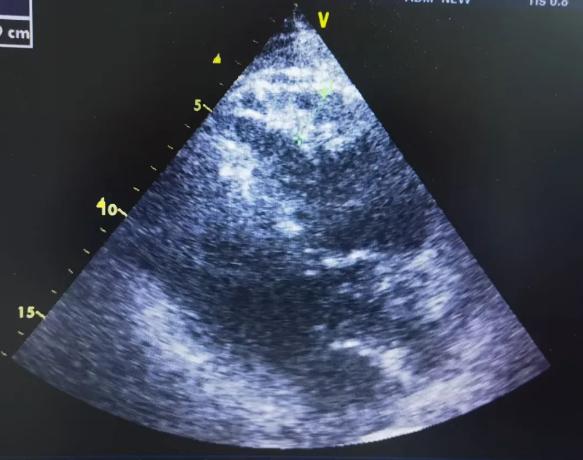

在此基础上,迅速完善24小时动态心电图、超声心动图、冠脉造影等检查,排除心肌炎、冠心病等病因,锁定心律失常高风险信号,高度怀疑患者为ARVC患者。

为明确疾病诊断,心内科团队在科室主任郭丽君的带领下,迅速启动多学科会诊机制,联合北医三院心内科刘书旺、曾辉教授,影像科专家王新宇教授远程讨论。专家们根据患者症状、心电图、超声心动图表现,考虑致心律失常型右室心肌病可能性大。面对这一高危病例,医院立即开通绿色通道,行心脏核磁共振(CMR)检查,最终通过CMR这一“金标准”确诊患者右心室扩大,心肌组织显著变性,符合ARVC典型特征表现。